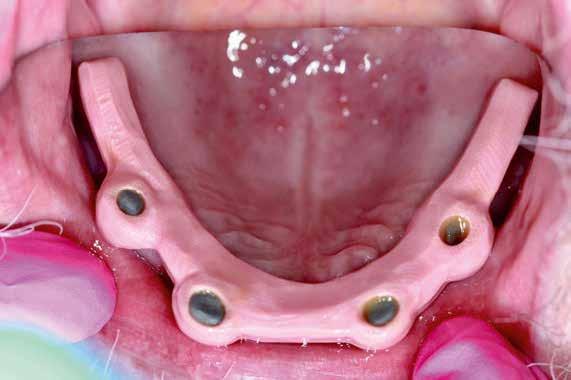

A páciens évekkel ezelőtt két mukozális megtámasztású kivehető fogsort kapott. Az atrófia következtében ezek már nem rögzülnek megfelelően. Implantátumokat terveztünk pillérként. A csekély csontkínálat és az egyszerűbb kezelhetőség okán négy rövid implantátumot (Bicon, Bosten) helyeztünk be. Végleges pótlásként teleszkóp elhorgonyzású redukált alaplemezű kivehető fedőfogsort terveztünk. A fogorvos intraorális szkennerrel beolvasta az alsó és felső állcsontot. Ehhez becsavarta az implantátumokba a megfelelő scanbody-kat (digitális lenyomatvételi fej - a ford.) (rövid UA-Scan-post, Bicon, 2. kép). Mivel a régi fogsorral komfortosnak érezte a harapást a páciens, ez segített a harapásregisztrációban. A helyzet rögzítésére vesztibulárisan beszkennelte az orvos a behelyezett fogsorokat. Végül a két fogsort szájon kívül is, egészében beolvasták a Medit IO-szkennerrel (Szöul). Utoljára portréfotó

készült. Minden így nyert adatot interneten a laboratóriumba küldtek. A végleges elkészítéséig a páciens hordja tovább régi fogsorait. Nem volt szükség további találkozásokra sem ideiglenes fogsor készítéséhez, sem a harapásregisztrációhoz és laborban készített sablonok próbájához sem.

Fogtechnikai labor:

A laboratóriumban az összes adatot összefűztük egy „digitális pácienssé” a darmstadti exocad DentaCad rendszerében. Az állcsontokat a vesztibuláris fogsorbeolvasással illesztettük térben egymáshoz (3. kép). Az implantátumok helyzetét a fejek mutatták meg. A külön beszkennelt fogsorokat pedig mock-up-ként tudtuk használni a tervezés során (4. kép). A páciens portréját rávetítettük a frontra, így segítve az esztétikai ellenőrzést (5. kép)

Az állcsontok 3D adataiból digitális munkamintákat készítettünk, majd kinyomtattuk ezeket DLP-3D nyomtatóval (6. kép). A digitális mintakészítés technikai analóg implan-

A tervezés a felépítmények kialakításával kezdődött (7. kép). Ezeket CNC-marással valósítottuk meg. Az előzetesen félkész felépítménytömböket szinte egyetlen lépésként még „analóg” munkáltuk meg. Ehhez becsavaroztuk azokat a munkamintára, majd a frézgépben 2 fokosra kúposra frézeltük a falakat (8. kép). Ezt a helyzetet asztali szkennerrel beolvastuk, majd az új 3D adatokat virtuálisan ráfűztük a digitális páciensre. A felépítményekre sapkák készültek. A sapkákra terveztük 0,07 mm-es helyfenntartással a stégeket (9. kép)

A stégek minimális falvastagsága 1 mm, keresztmetszete minimum 7 mm2. A helykínálatot a régi fogsorok rávetítésével tudtuk ellenőrizni (10. kép). Végül a sapkákat nem nemesfémötvözetből martuk ki. A stégek marása a bostoni Bicon cég Trinia nagy teljesítményű műanyagából történt meg (11. kép). Ez a műanyag térhálósan üvegszál-erősítésű. Ezáltal kiemelkedően magas a hajlítószilárdsága, ebből fakad a későbbi fogsor törőszilárdsága. A Trinia további előnye jó kötésképző képessége más műanyagokkal. A szükséges kötési szilárdság eléréséhez nincs szükség adhezívre vagy opákerre, mint a fémvázaknál. Mivel a Trinia-blokkok fog- és ínyszínben is hozzáférhetők, esztétikai okokból végzett opákerezésre sincs szükség (12. kép). A stégre tervezzük a fogsort (13. kép). A stég és a fogsor között 0,07 mm-es hézagot hagyunk. A konstrukció

Fogorvos:

A behelyezőkulcs segítségével rakják be a felépítményeket az implantátumokba. Ezután a fémsapkák kerülnek a helyükre. A Trinia stéget rájuk illesztve csúsztató-ragasztóval összeragasztjuk direktben azokkal (16. kép). Végül a fogsor esztétikai